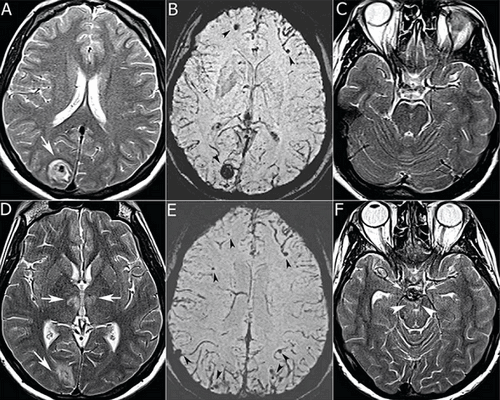

Неходжкинская лимфома (случай сочетанного поражения глаз и орбиты)

В статье представлен полный клинический, инструментальный и морфологический анализ крайне редкого патологического состояния — сочетанного поражения глаз и орбиты лимфопролиферативным процессом.

Мужчина 52 лет обратился в нашу клинику с жалобами на выстояние левого глаза и двоение в течение 2 мес. Проведен анализ клинической симптоматики. Инструментальные методы исследования включали флюоресцентную ангиографию (ФАГ) (Digital retinal Camera CX-1, «Canon», Япония), высокоразрешающее ультразвуковое дуплексное сканирование (УЗДС) (Voluson 730 Pro, «General Electric Healthcare», Австрия), компьютерную томографию (КТ). Диагноз верифицирован с помощью цитологического и гистологического (отделение патогистологии института, руководитель — проф. И.П. Хорошилова-Маслова) методов исследования.

При осмотре пациента отмечены легкий отек век и периорбитальных тканей слева, стационарный экзофтальм слева (асимметрия между двумя глазами 3 мм), ограничение подвижности левого глаза по горизонтали, в крайних отведениях (рис. 1). Внутриглазное давление обоих глаз в пределах нормы. Зрение обоих глаз 1,0 со слабой миопической коррекцией. Передний отрезок глаз — без изменений, стекловидное тело прозрачное. Периметрия позволила выявить единичные относительные скотомы в центральной зоне левого глаза, поля зрения правого глаза были в пределах нормы.

При офтальмоскопии слева отмечен желтоватый фон глазного дна. Артерии сетчатки сужены и извиты, вены сужены, выпрямлены. Легкий прозрачный отек сетчатки по ходу основных крупных сосудистых пучков сетчатки и у диска зрительного нерва. Визуализируются крупные, неправильного хода, резко извитые новообразованные сосуды. В субретинальном пространстве определялось образование желтоватого цвета, диффузно распространяющееся кверху и книзу от диска зрительного нерва без вовлечения в процесс макулярной зоны (рис. 2, а). В артериальную фазу ФАГ определялась крупнопятнистая гиперфлюоресценция центрального отдела глазного дна до средней периферии с наиболее выраженными изменениями в перипапиллярной зоне (см. рис. 2, б).

При осмотре глазного дна правого глаза также определялся желтый оттенок глазного дна (менее выраженный, чем слева), отмечались нарушение хориоидального рисунка, прозрачный, диффузный легкий отек сетчатки, которые более отчетливо визуализировались на ФАГ (рис. 3, а, б).

КТ позволила выявить ретробульбарную ткань с достаточно четкими границами, локализующуюся вокруг зрительного нерва, а также утолщение хориоидеи слева (рис. 4). Патологических изменений справа по данным КТ выявлено не было. С помощью УЗДС слева в В-режиме непосредственно за задним полюсом глаза (вокруг зрительного нерва) определяли гипоэхогенную, практически однородную опухолевую ткань с четкими неровными контурами. Одновременно выявили диффузное утолщение хориоидального слоя в области заднего полюса глаза — до 2,5 мм (рис. 5, а). Ультразвуковой денситометрический анализ, проведенный на основе двумерных серошкальных гистограмм, продемонстрировал крайне низкие значения акустической плотности ткани (А=3—12 усл. ед.) (см. рис. 5, б). В режиме цветового допплеровского картирования (ЦДК) отмечена гиперваскуляризация ретробульбарного и интраокулярных очагов с высокими линейными характеристиками кровотока. Следует отметить, что два указанных процесса — внутриглазной и орбитальный имели единую васкуляризацию (см. рис. 5, в). Патологических изменений в правом глазу по данным ультразвукового исследования выявлено не было.

Рис. 4. Компьютерная томограмма орбит в аксиальной (а) и сагиттальной (б) проекциях.

Рис. 5. Результаты дуплексного сканирования. а — утолщение хориоидеи; б — денситометрические показатели акустической плотности опухоли в В-режиме; в — множественные собственные сосуды опухоли, единая васкуляризация внутриглазного и орбитального очагов в режиме ЦДК.

Данные клинического и комплексного инструментального обследования позволили предположить лимфому с одномоментным вовлечением глаза и орбиты слева и начальный процесс с правой стороны.

Для подтверждения диагноза и определения дальнейшей тактики ведения больного первым этапом лечения была эксплораторная орбитотомия с биопсией образования. Во время операции непосредственно за глазным яблоком выявлена диффузно распространяющаяся опухолевая ткань светло-розового цвета с выраженной собственной сосудистой сетью, инфильтрирующая мягкие ткани орбиты, интимно контактирующая с задним полюсом глаза и оболочками зрительного нерва. Цитологически, иммуноцитохимически и гистологически была верифицирована В-клеточная лимфома (рис. 6), в связи с чем больной был направлен на консультацию к онкогематологам и нейрохирургам. Полное обследование у этих специалистов (включающее в том числе стернальную пункцию и магнитно-резонансную томографию головного мозга) не выявило патологии в других системах органов, в связи с чем процесс был расценен как первичная лимфома органа зрения с вовлечением обоих глаз и левой орбиты. Больному был назначен курс полихимиотерапии (ПХТ).

Рис. 6. Морфологическая картина. а — результат цитологического исследования. Обилие пролимфоцитов. Окраска по Паппенгейму. Ув. 1000; б — результат иммуноцитохимического исследования. Выраженная положительная реакция на CD20 (коричневое окрашивание); в — гистологический препарат. Окраска гематоксилином и эозином. Ув. 100 и 400. Разрастание лимфоидных клеток средних размеров (в 1,5 раза крупнее малых лимфоцитов) с ядрами округлой и неправильной формы, дифференцируются немногочисленные клетки более крупных размеров.

Сочетанное поражение глаза и орбиты НХЛ — крайне редкое явление. Как правило, диагностика орбитальной лимфомы не вызывает серьезных трудностей. В большинстве случаев клинико-инструментальная диагностика позволяет заподозрить лимфопролиферативный процесс. Диагностические ошибки могут иметь место при небольших периневрально расположенных образованиях, симулирующих опухоль зрительного нерва [22, 23], а также при перибульбарных лимфомах, которые нередко могут расцениваться как задний склерит [24].

Значительные сложности возникают в диагностике внутриглазного процесса. Офтальмоскопическая картина не однозначна и может симулировать ряд воспалительных процессов (так называемый «маскарадный синдром») [13]. Описаны случаи первичной внутриглазной лимфомы, симулирующей гранулематозный пантувеит, витриит и диффузный васкулит сетчатки [14]. Нередко внутриглазная лимфома симулирует метастатические опухоли хориоидеи, хориоидальную эффузию при заднем склерите [11, 14—16].

Следует обратить внимание, что в нашем случае внутриглазные очаги локализовались в хориоидее (менее типичная локализация для первичной лимфомы), в то время как сетчатка и стекловидное тело (наиболее частая локализация внутриглазной лимфомы) оставались интактными.

Из инструментальных методов исследования следует признать высокую информативность УЗДС, демонстрирующего типичные признаки лимфопролиферативного процесса: практически однородный гипоэхогенный очаг с выраженной «густой» собственной сосудистой сетью, с высокими линейными скоростными характеристиками кровотока в них. ФАГ оказалась наиболее чувствительным и единственным инструментальным методом, позволившим выявить начальный туморозный процесс в правом глазу.